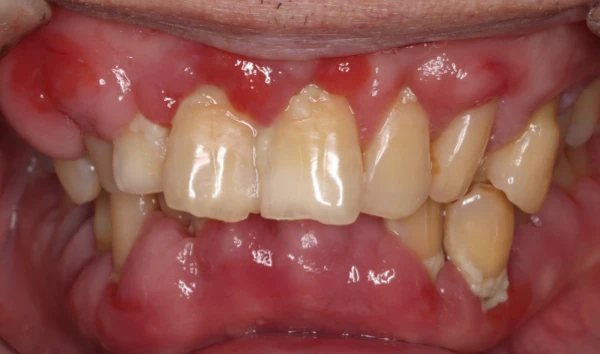

重度歯周病の治療法

歯周病とは、原因の一番は細菌感染により引き起こされるものです。FMD(フルマウスディスインフェクション)とは、一回の治療で歯茎の中の汚れを超音波などの器具を用いて除去し、また同時に抗菌薬を投与して、口腔内の細菌を一度に除去する方法です。そのため治療回数を少なくすることができる点、歯周外科治療を避けたい方にメリットがありあす。保険診療では、歯茎の中のクリーニングは4〜8回に分けて行われることが多いため、クリーニングを行ったところにまた炎症が波及してしまうことがあります。FMDでは、一度にクリーニングすることにより、口腔内の炎症を一気に沈静化することが期待されます。

歯周組織再生療法

歯を残す最新治療

歯周病により破壊された、歯茎や骨を人工骨や成長因子などを用いて再生させる治療方法です。

将来的に抜歯となるリスクの高い歯などを歯周組織を再生させ、歯を長持ちさせることを目的とします。歯周病でダメになった歯をどうしても残したい方、歯ぐきや歯槽骨を元に戻して歯の寿命をしっかり伸ばしたい方に適応される治療方法です。 -

審美歯周病治療

見た目も美しく

歯周病治療を行うと歯茎が下がったとよく聞きます。残念ながら、炎症が長期に渡り存在していた歯茎や、重度歯周病では、治療を行うことにより歯茎が下がり炎症が除去されると歯茎が下がってしましやすいです。そういった場合、セラミックス治療を行うことで審美的に改善を図ることがあります。

また、歯周病はないのに、歯茎が下がってしまうことによる審美性が損なわれてしまう病気があります。そのような場合、歯茎の移植などを行うことにより、歯を削ることなく審美性を改善させることができます。 -